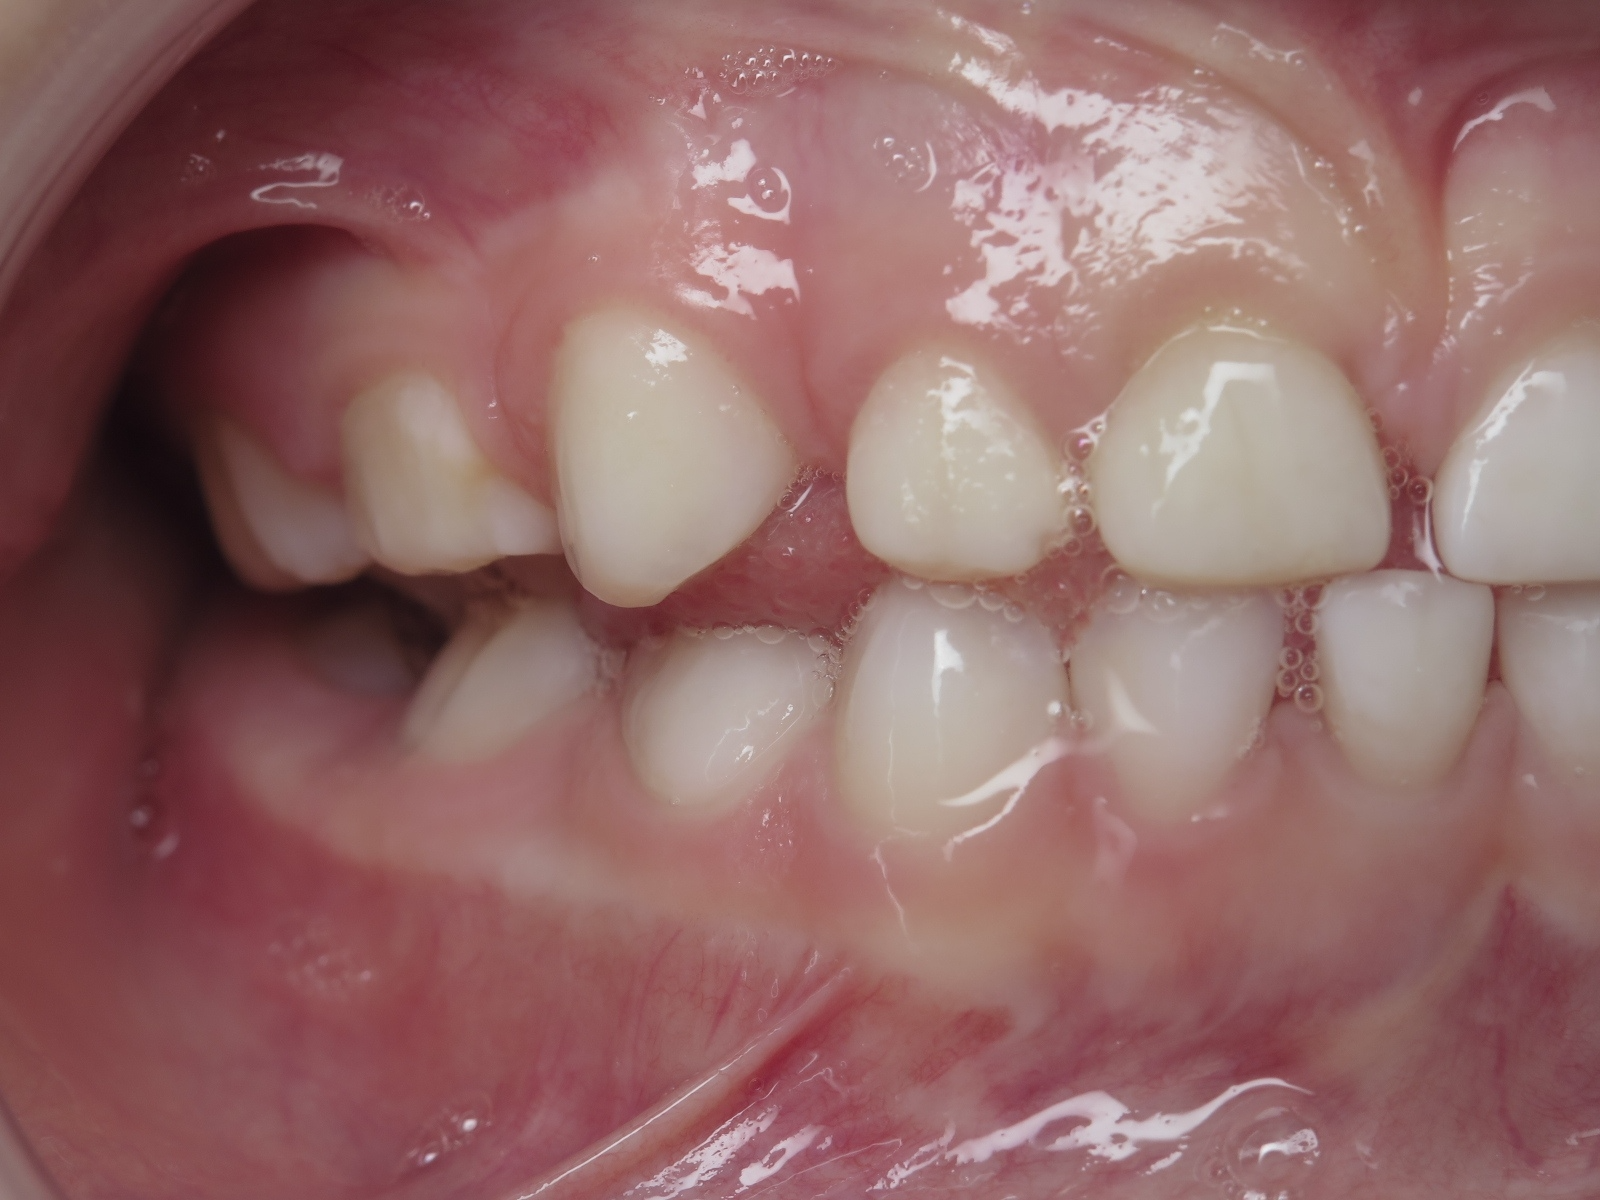

7.inversé droit 4 ans

inversion des dents postérieur coté droit